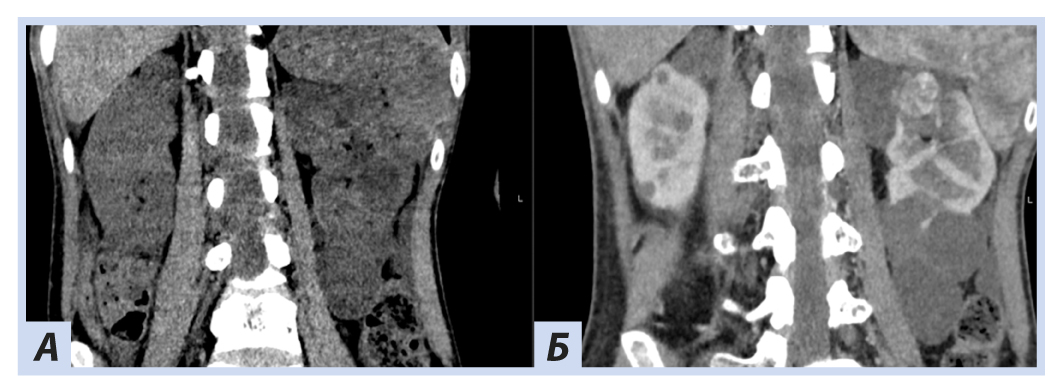

При скрининговом ультразвуковом исследовании забрюшинного пространства были выявлены изменения обеих почек, которые были интерпретированы как множественные кисты при дообследовании на КТ забрюшинного пространства: множественные кистозные образования обеих почек; в верхнем полюсе левой почки — кистозно-солидное образование, изоденсное паренхиме почки в нативную фазу (40 HU), в артериальную активно накапливающее контраст (до 100 HU), контуры его четкие неровные (рис. 5, 6).

Рис. 5. Пациентка П., 30 лет, с диагнозом «Болезнь Гиппеля−Линдау»: компьютерная томография забрюшинного пространства

Примечание. А — нативная фаза: кисты обеих почек, солидный узел в верхнем полюсе левой почки; Б — артериальная фаза: кисты обеих почек более отчетливы на фоне контрастированной почечной ткани, солидный узел в верхнем полюсе левой почки с неоднородным накоплением контраста опухолью.

Рис. 6. Пациентка П., 30 лет, с диагнозом «Болезнь Гиппеля−Линдау»: компьютерная томография забрюшинного пространства

Примечание. А — нативная фаза: кистозно-солидное образование левой почки; Б — артериальная фаза: кистозно-солидное образование левой почки с неоднородным накоплением контраста опухолью.